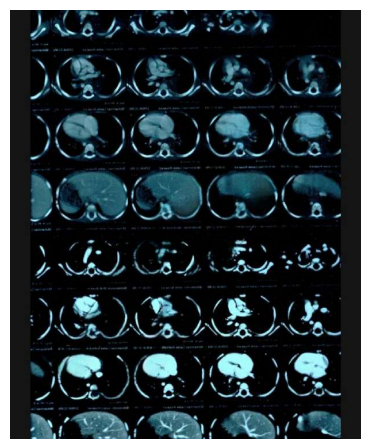

A contrast-enhanced Computer Tomography Scan of the chest showed: a large mass filling the posterior mediastinum in it's upper and middle parts, aligned with the visceral side of the right upper lobe.

MRI showed: a mass in the posterior mediastinum surrounding the tracheal branch and reaches the diaphragm, surrounding the Azygos vein, superior vena cava, aorta, major vessels and esophagus, measuring (11*5*7) cm. and foci osteolysis in the 9,11,12 thoracic vertebrae.

With an annual periodic review, for blood tests and a chest CT scan that showed a decrease in the size of the lymphangioma.

With an annual periodic review, for blood tests and a chest CT scan that showed a decrease in the size of the lymphangioma